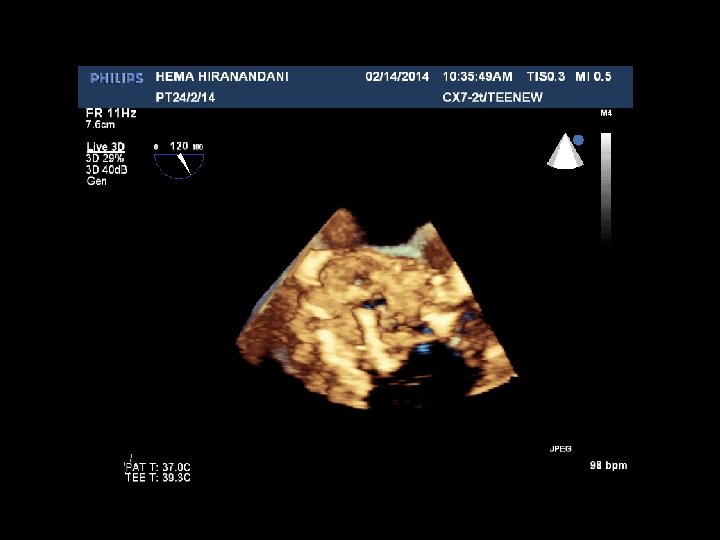

HEMA HIRANANDANI F 57 YRS • • • AVR BIO PROSTHETIC VALVE DEHISCENCE IE MULTIPLE VEGETATIONS ON BIO PRO VALVE AO ROOT ABSCESS SEVERE PARAVALVULAR AR RVSP= 37 mmhg

Hema Hirandani